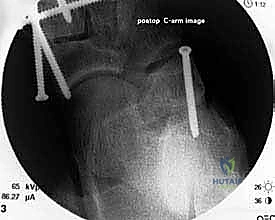

إطالة العمود الجانبي للقدم، أو قطع عظم إيفانز، هو إجراء جراحي حيوي لتصحيح تشوه القدم المسطحة المكتسبة الناتج عن قصور الوتر الظنبوبي الخلفي. يهدف إلى استعادة قوس القدم وتخفيف الألم وتحسين وظيفة القدم، ويتم على يد خبراء مثل الأستاذ الدكتور محمد هطيف.

في هذا الدليل المرجعي، سنسلط الضوء بشكل مكثف على الحل الجراحي المتقدم والفعال المعروف باسم إطالة العمود الجانبي للقدم (Lateral Column Lengthening)، وتحديداً التقنية الجراحية الدقيقة المسماة "قطع عظم إيفانز" (Evans Osteotomy). يُعد هذا الإجراء حجر الزاوية في استعادة الميكانيكا الحيوية الطبيعية للقدم، وإعادة بناء القوس المنهار، وتخفيف الألم بشكل دائم.

* الأشعة السينية (X-rays) مع تحمل الوزن: ضرورية لتقييم درجة انهيار القوس وزوايا العظام (مثل زاوية تالونافيكولار Meary's Angle).